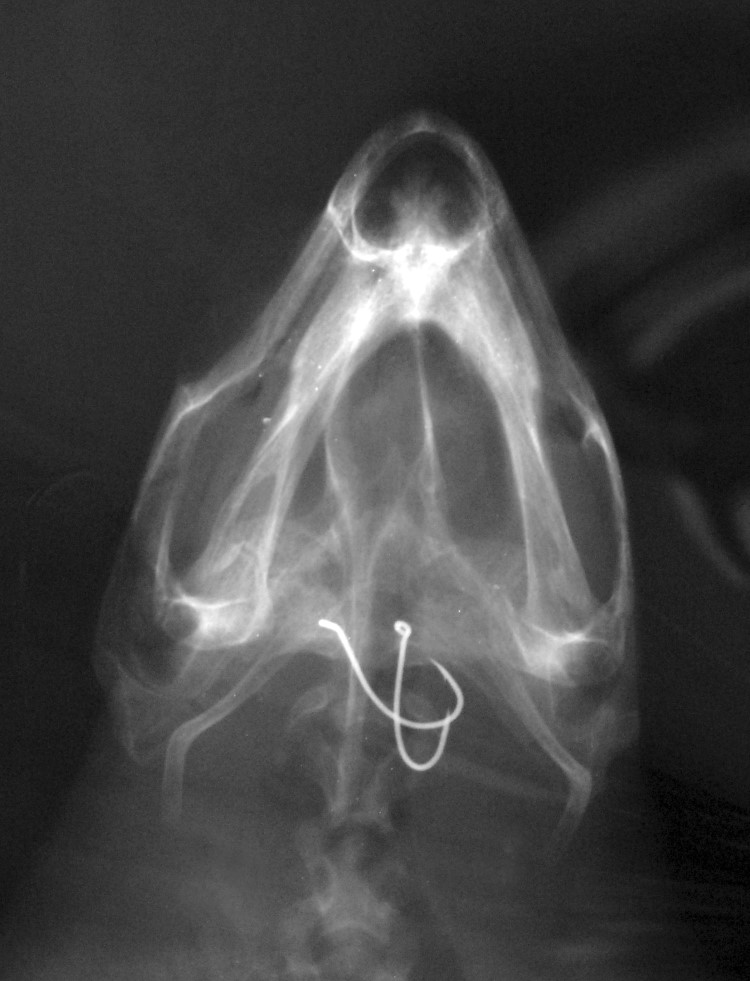

Slika 6 – RTG glavate želve sa udicama